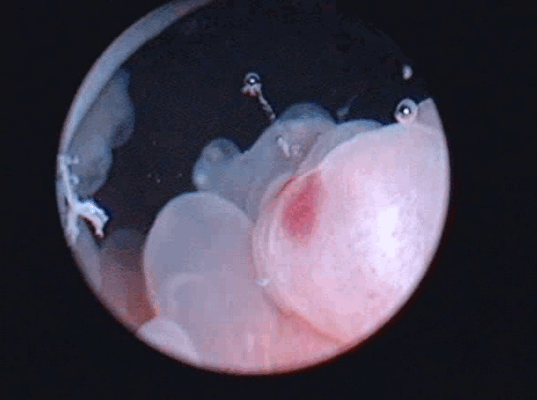

Цистоскопическое обследование пациентки О.

Цистоскопическая картина солидного образования

Цистоскопическое обследование пациента М.

Цистоскопическая картина солидного образования, вдающегося в полость мочевого пузыря в виде массивных бугристых масс, покрытых отечной слизистой оболочкой с очагами кровоизлияний, с явлениями распада и инкрустации солями